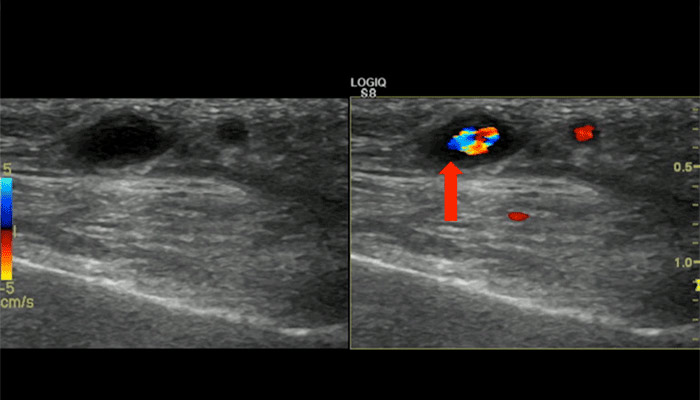

Ultrasound view of the parietal branch of the temporal artery, seen on cross-section. The dark area surrounding the blood vessel is called the “halo sign”, and indicates swelling of the wall of the vessel due to giant cell arteritis.